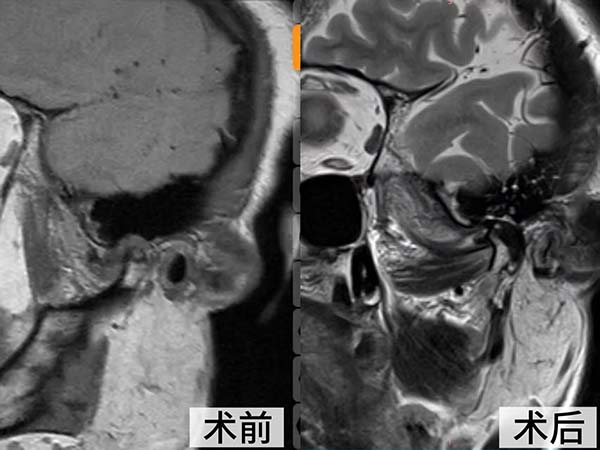

经详细检查,她的症状被确诊为 “左侧颞下颌关节不可复性盘前移位”,关节盘已严重变形、粘连伴髁突骨折破坏,必须通过外科手术才能从根本上解决问题。

面对这一复杂病例,口腔颌面整形创伤外科主任王学玖组织团队开展多次术前讨论。鉴于患者关节结构破坏严重,常规的关节镜微创手术已难以奏效,团队最终决定为其施行开放性颞下颌关节手术。

王学玖团队在患者耳前设计了精巧的隐蔽切口,娴熟地避开重要神经血管,充分暴露病变的颞下颌关节,清晰地见到关节盘已完全脱位并粘连于前内侧,盘后区组织糜烂。团队精准地完成了关节盘的松解、复位与固定,重建了正常的关节结构。

术后,司女士恢复良好,困扰多年的关节区疼痛显著缓解,张口度也较之前明显改善。目前,在医护人员的精心治疗和护理下,她已开始准备进行系统的张口训练,并对未来的生活质量充满了信心。“今后终于能踏实地吃一顿饭了!”